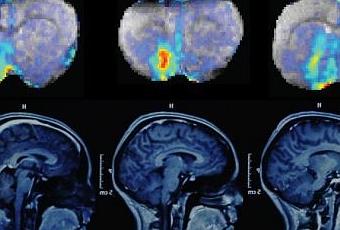

Investigadores del MIT han dado un paso hacia esa meta y han establecido una técnica que les permite rastrear la comunicación neuronal en el cerebro a través del tiempo, el uso de imágenes de resonancia magnética (MRI), junto con un sensor molecular especializado. Esta es la primera vez que alguien ha sido capaz de asignar las señales neuronales con alta precisión sobre las regiones cerebrales grandes en animales vivos, ofreciendo una nueva ventana en la función del cerebro.

Para el seguimiento de la función de la dopamina en la comunicación neuronal, los investigadores usaron un sensor de resonancia magnética que habían diseñado anteriormente, que consiste en una proteína que contiene hierro que actúa como un imán débil. Cuando el sensor se une a la dopamina, sus interacciones magnéticas con el tejido circundante se debilitan, lo que atenúa la señal de MRI del tejido. Esto permite a los investigadores ver en qué parte del cerebro de la dopamina está siendo liberada. Los investigadores también desarrollaron un algoritmo que les permite calcular la cantidad exacta de dopamina presente en cada fracción de un milímetro cúbico del estriado ventral.

Después de entregar el sensor de resonancia magnética para el cuerpo estriado ventral de las ratas, el equipo estimuló eléctricamente la vía mesolímbica y fue capaz de detectar exactamente donde la dopamina en el estriado ventral fue lanzada. Un área conocida como núcleo accumbens y conocida por ser uno de los principales objetivos de la dopamina en el área tegmental ventral, mostraron los niveles más altos. Los investigadores también vieron que la dopamina también se libera en las regiones vecinas, como el pálido ventral, que regula la motivación y las emociones, y las partes del tálamo, que retransmite las señales sensoriales y motoras en el cerebro.

Cada estimulación de la dopamina se prolongó durante 16 segundos y los investigadores tomaron una imagen de resonancia magnética cada ocho segundos, lo que les permite realizar un seguimiento de los niveles de dopamina y cómo el neurotransmisor se liberó de las células y luego desapareció. Incluso pueden dividir el mapa en diferentes regiones de interés y determinar la dinámica de forma separada para cada una de esas regiones.